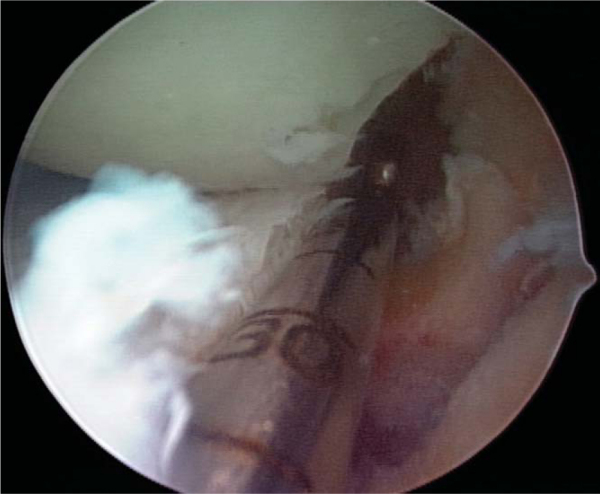

Slot orientation follows the normal anatomy of the meniscus attachment sites. By use of electrocautery, the centers of the anterior and posterior horn attachment sites are connected with a line. With this line as a guide, a 4-mm bur is used to make a reference slot in the tibial plateau. Its height and width will equal the dimensions of the bur, and its alignment in the sagittal plane should parallel the slope of the tibial plateau (

Fig. 47-5

). Slot dimensions should be confirmed by placement of a depth gauge in the reference slot, which also measures the anteroposterior length of the tibial plateau (

Fig. 47-6

). With use of a drill guide, a guide pin is placed just distal and parallel to the reference slot (

Fig. 47-7

) and advanced to but not through the posterior cortex. The pin is subsequently overreamed with a 7- or 8-mm cannulated drill bit (

Fig. 47-8

), again with care taken to maintain the posterior cortex. A box cutter is then used to make a slot 7 to 8 mm wide by 10 mm deep (

Fig. 47-9

), which is smoothed and refined with a 7- to 8-mm rasp to ensure that the bone bridge will slide smoothly into the slot (

Fig. 47-10

).